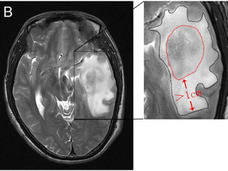

Steroids May Limit the Effectiveness of Immunotherapy for Brain Cancer

In people with glioblastoma and other brain cancers, steroids appear to limit the effectiveness of immunotherapy drugs, a new study shows. The findings should influence how steroids are used to manage brain tumor symptoms, researchers said.

-